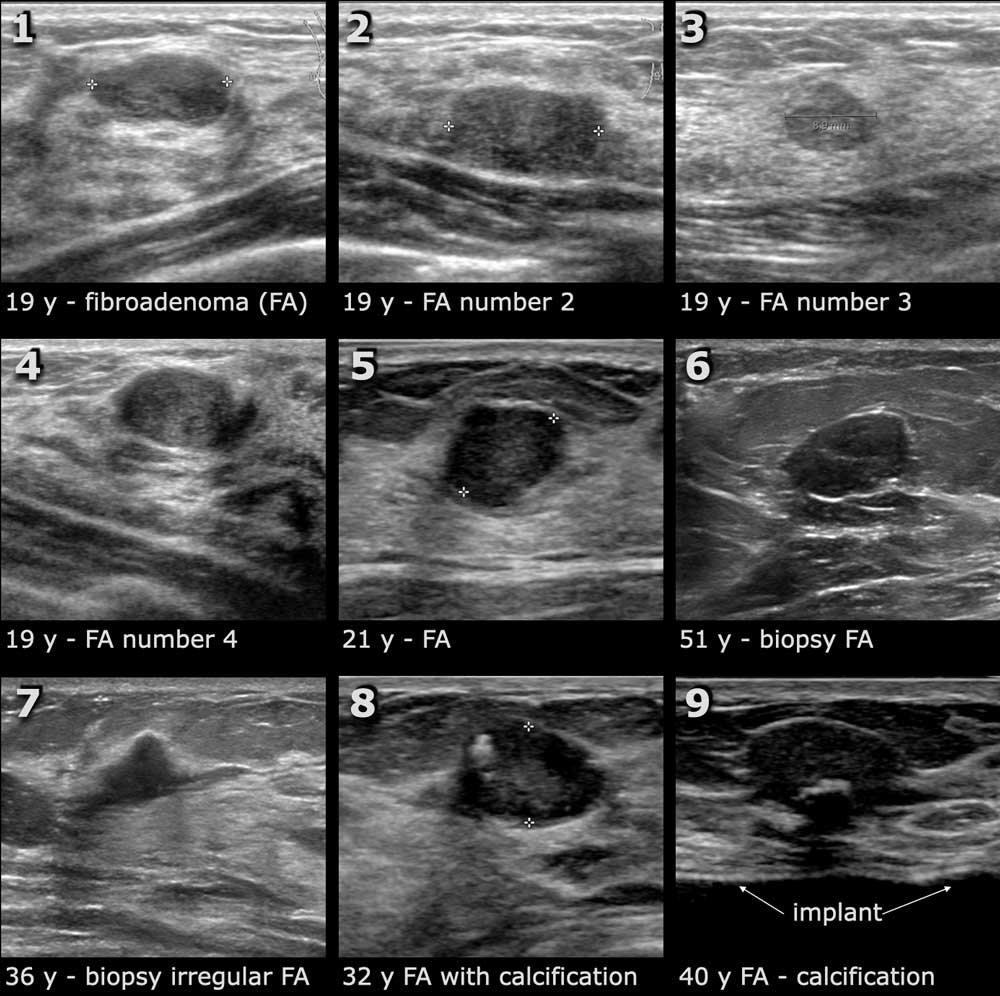

This is where breast ultrasound comes into play, offering a non-invasive, radiation-free solution for early detection and monitoring of breast health issues. For women like Anjali, who may feel apprehensive about mammograms or are too young for regular screenings, breast ultrasound provides a much-needed alternative that is both practical and emotionally reassuring.

The breast ultrasound service is not just a diagnostic tool; it’s a lifeline for women worried about their breast health. This service is particularly beneficial for younger women or those with dense breast tissue, where traditional mammograms might not be as effective. The clarity and peace of mind that comes from understanding one’s health status cannot be overstated.